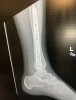

amazing what can be done with a cordless screwdriver and some coated deck screws!I hope they used the same Terminator type shit on Nurk that they did with THE HCP Jr.

I AM Mexican remember.amazing what can be done with a cordless screwdriver and some coated deck screws!

ok...so add in stucco and mortarI AM Mexican remember.

More like Bondo.ok...so add in stucco and mortar

Did you do that yourself?I hope they used the same Terminator type shit on Nurk that they did with THE HCP Jr.

Pardon my ignorance, but when you have screws or plates etc put into you like this, are they eventually removed?

Usually they are kept inside. There are some rare circumstances that will cause them to have to be removed.Pardon my ignorance, but when you have screws or plates etc put into you like this, are they eventually removed?